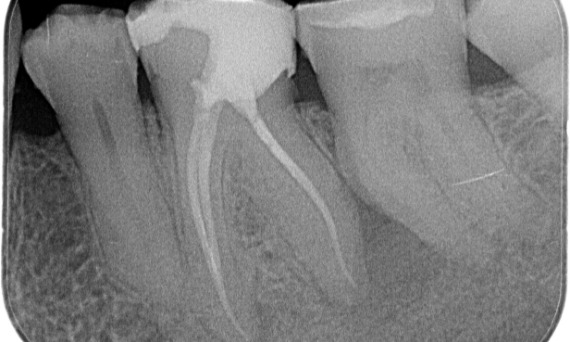

Antes: Radiolucencia periapical asociada principalmente con la raíz distal y pérdida de la lámina dura en la raíz mesial.

Después: En este caso, se eligió TruNatomy para permitir un enfoque apalancado en las caries y un enfoque en la conservación de la dentina pericervical, especialmente en el aspecto mesial donde el diente tuvo una restauración más mínima.